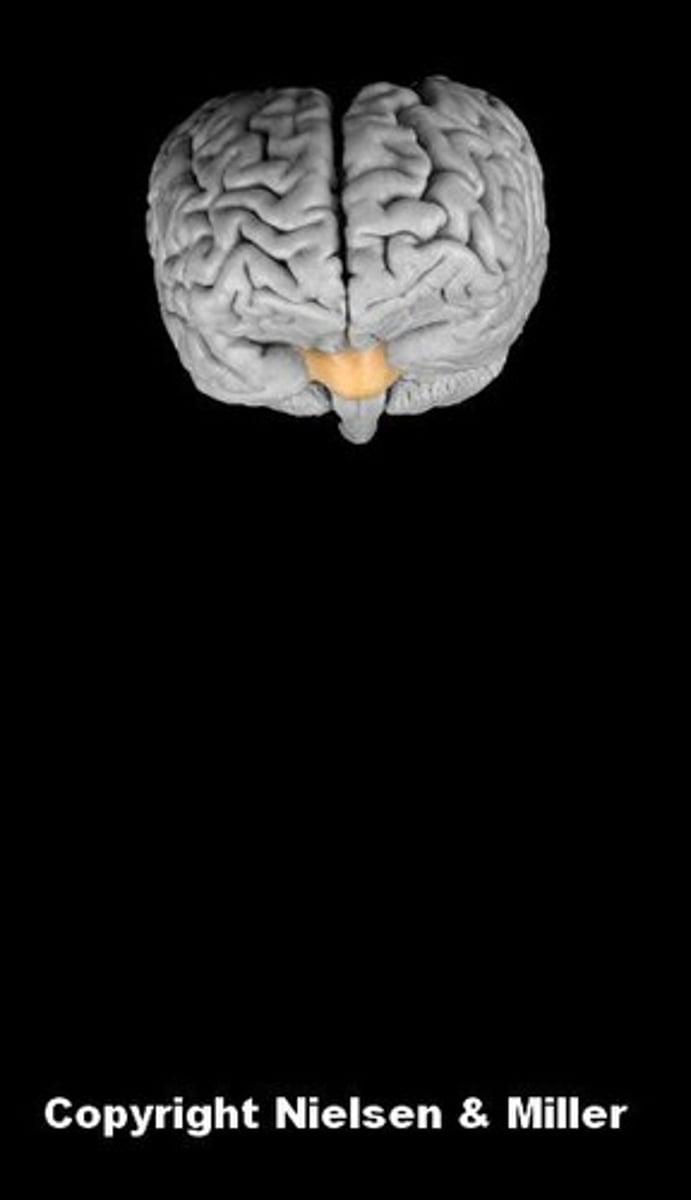

brain

cerebellum

cerebral hemispheres

cerebrum

fourth ventricle

hypothalamus

lateral ventricles

medulla oblongata

midbrain

pons